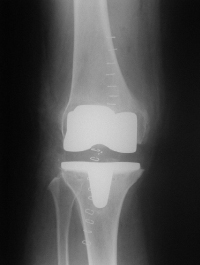

膝は上から太ももの骨(大腿骨)とすねの骨(脛骨)と お皿の骨(膝蓋骨)から出来ていますが、 矢印のように内側の大腿骨と脛骨のあいだのすきまが接触しています。 これが軟骨が磨耗している状態です。 これに人工関節を入れたのが下の写真です。 |

大腿骨と脛骨の表面に白く写っている金属をいれており、 その間のすきまにはプラスティックが入っているので 歩行のときの痛みがなくなります。 |